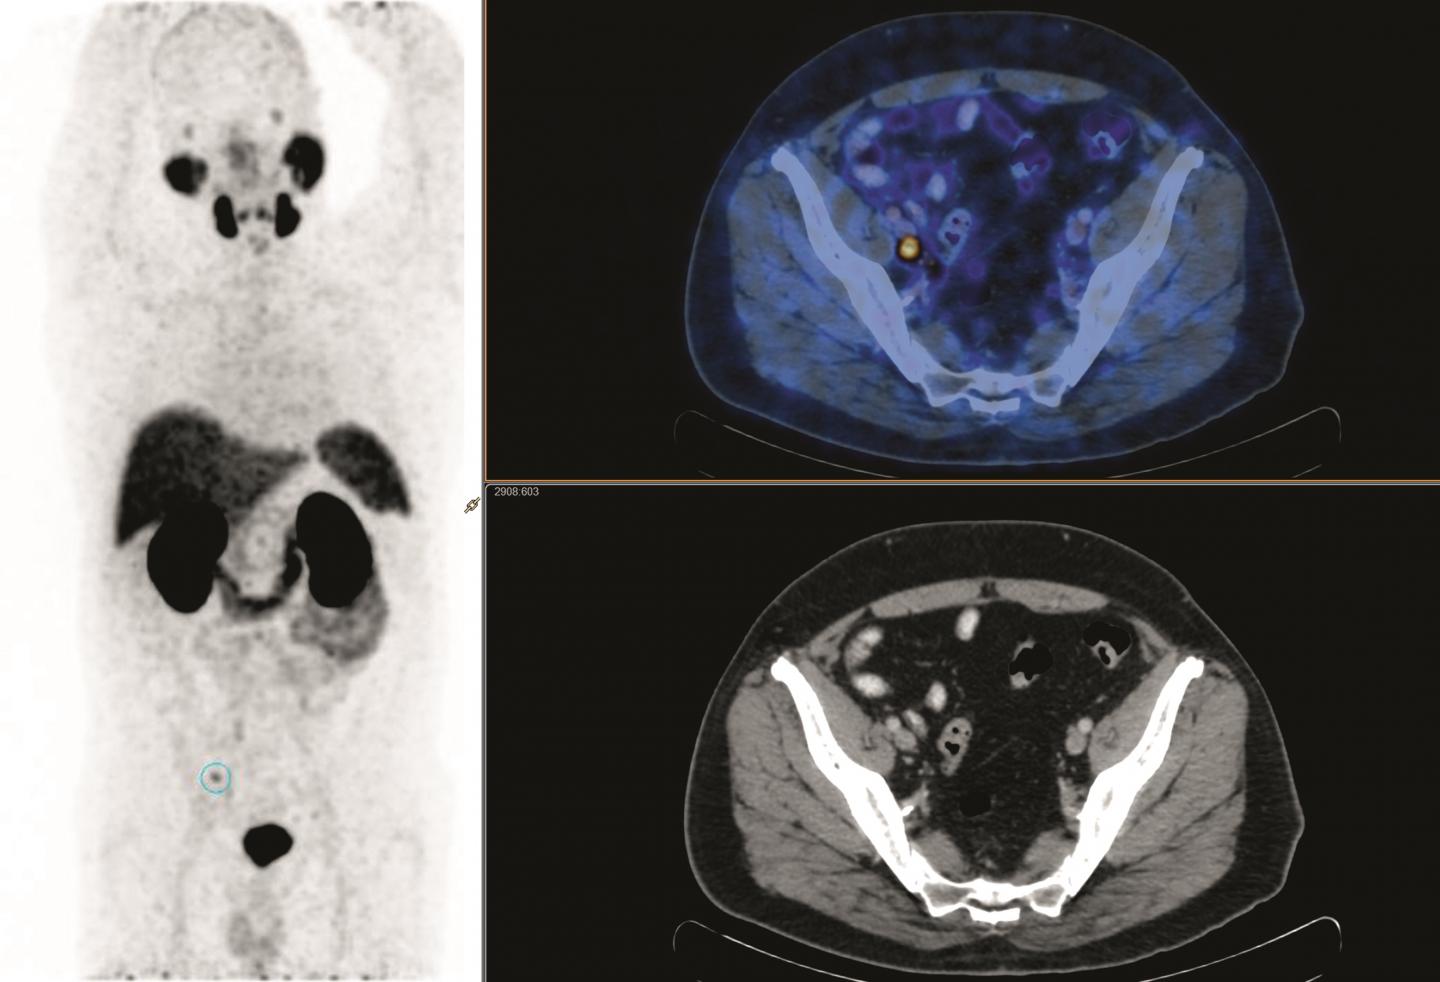

The therapy is an individualized treatment. Radioligand therapy with lutetium-177 prostate specific membrane antigen 177 LuLu-PSMA represents a promising treatment for metastatic castration-resistant prostate cancer patients. There is now a solid body of evidence for the performance of 68Ga-PSMA PETCT in primary and secondary staging with an ability to accurately detect small volume disease at far lower serum PSA levels the use of 68Ga-PSMA PETCT as a.

Anzeige Clinically Proven Herbal Treatment Relieves Prostatitis in 30 Days. Prostate-specific membrane antigen PSMAbased imaging seeks to fill some critical gaps in prostate cancer staging and response assessment and may select patients for treatment with radiolabeled PSMA conjugates. Lu-177-PSMA therapy for metastasized prostate cancer.

The recent development of radiotracers directed against prostate-specific-membrane-antigen PSMA has taken things to a new level. Anzeige Mit dem PROSTAFIX Programm Prostatitis Beckenschmerzsyndrom behandeln. Anzeige Prostatricum Kapseln - Prostatitis für 1 Kurs loswerden.